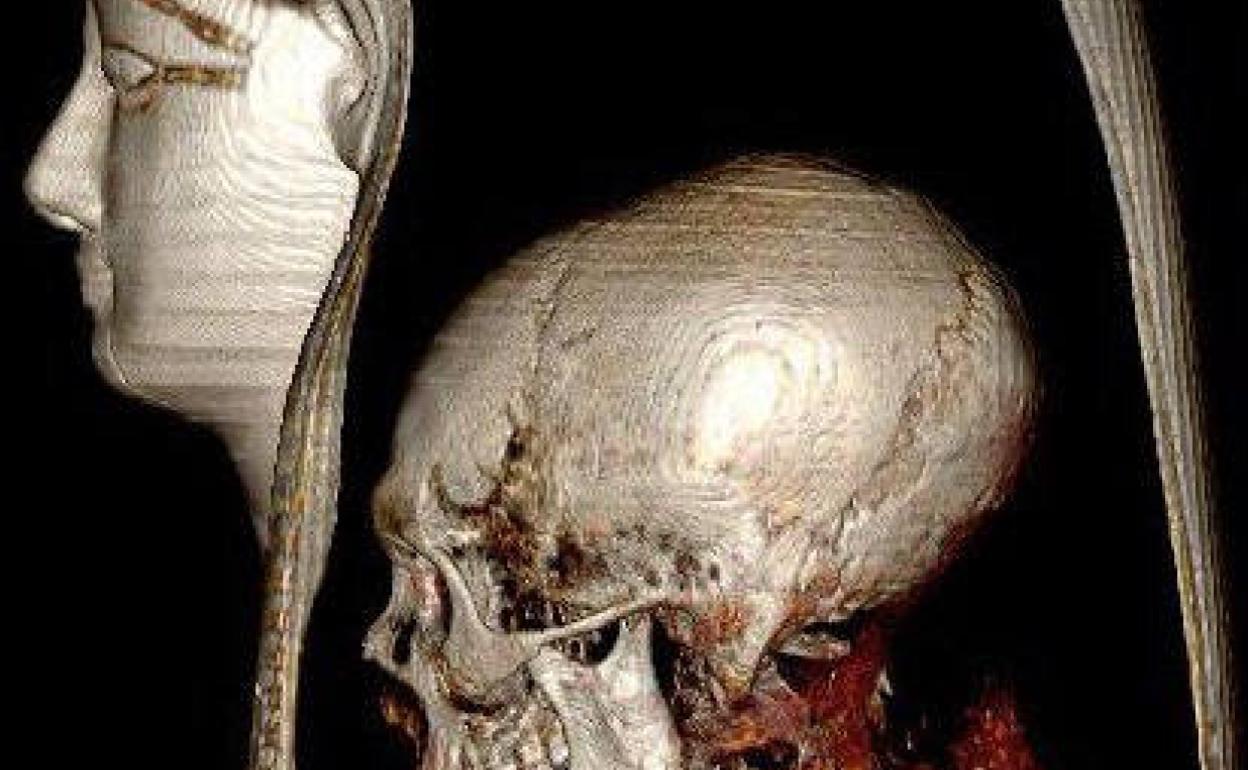

El escáner muestra el cráneo de Amenofis I, muerto con 35 años. EP

No pesaba ninguna maldición sobre la única momia de la realeza egipcia que mantenía intacto su envoltorio entre las muchas halladas en los siglos XIX y XX. Un sudario de vendas que los científicos de la Universidad de El Cairo han desliado gracias la Tomografía Axial Computarizada (TAC), técnica que permite ver qué hay bajo el sudario de la momia, primorosamente envuelta, decorada con guirnaldas de flores y con el rostro y el cuello bajo una delicada máscara de gran realismo con incrustaciones de piedras de colores.

Sabemos ahora que el faraón murió con 35 años, aunque no se ha hallado ninguna herida, traumatismo o lesión que pudiera ser la causa de su muerte. Los científicos han constatado que Amenofis I medía 1,69 metros, que mantenía una buena dentadura y que estaba circuncidado. Entre su ropaje mortuorio portaba 30 valiosos amuletos y una faja de oro, según explica Sahar Saleem, profesora en la Universidad de El Cairo, radióloga del Proyecto Momias Egipcias y autora del estudio forense junto al famoso egiptólogo Zahi Hawass. «Tenía un mentón estrecho, una nariz pequeña y fina, pelo rizado y dientes superiores ligeramente salientes», detalla Saleem, confirmado que Amenofis guardaba cierto parecido físico con su padre, Amosis o Ahmose I.